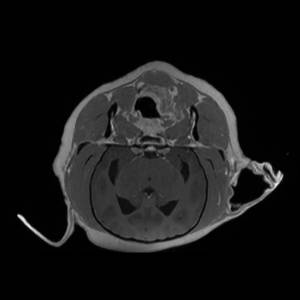

Main Gallery

Playing with a photo gallery function. It is possible to have multiple galleries, each within a namespace.